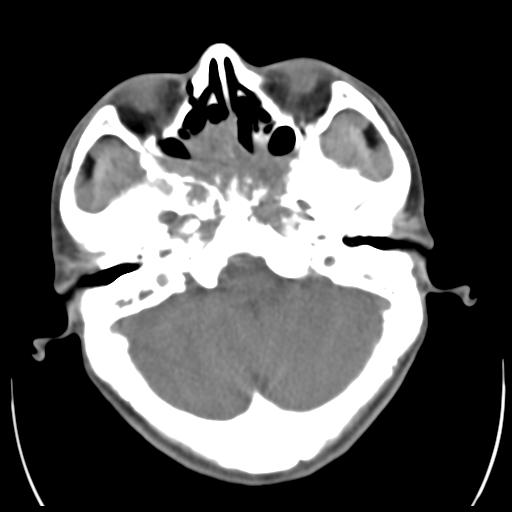

35m 鼻子时不时流血,头及右侧面部痛,颈部淋巴结未见明显大

骨窗

蝶窦,后组筛窦及鼻咽部团块状软组织影,骨壁破坏,病变较广泛。考虑恶性肉芽肿。建议活检。

颅底骨质明显破坏 支持鼻咽癌 但病灶的边缘毛糙 不能除外炎性

考虑中线肉芽肿(鼻硬结病),次之tb或真菌感染性肉芽肿,病变形态不像肿瘤,建议增强及活检。

蝶窦,后组筛窦及鼻咽部团块状软组织影,骨壁破坏,病变较广泛。考虑炎性肉芽肿性病变可能。建议活检。